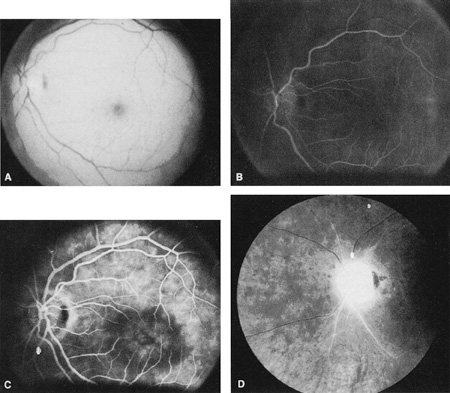

The clinical picture is typically striking. Patients present with a sudden painless loss of vision. The appearance of a cherry-red spot in the fundus is characteristic (Fig. 1).2 The cherry-red spot appears because soon after obstruction of the blood flow to the inner retina, the normally transparent retina becomes opaque and blocks the brownish-red color from the underlying choroid, which is still supplied by blood. Because the retina overlying the foveola is relatively thin, however, the normal color of the choroid is still visible in this area.3,4 Although characteristic, the cherry-red spot is not pathognomonic for central retina artery obstruction.5 Sometimes the characteristic cherry-red spot does not develop; there may be only a slight accentuation of the brownish-red color in the foveola.4 It is not known how long it takes this cherry-red spot to appear, but in a primate model, it has appeared as early as 30 minutes after obstruction.6 An afferent pupil defect is usually present.2

With time, the retinal opacity diminishes, generally leaving an optic nerve that is atrophic (Fig. 1). Frequently, thinned retinal arteries and veins also remain.7,8 No foveolar light reflex is evident, and a finely pigmented appearance of the macula is typical.7 In some cases, arterial collaterals develop at the optic disc.9–11 Rarely, anatomoses that exist between the central retinal artery and the ciliary arteries become visible as preretinal loops (Nettleship collaterals) after an occlusion at the edge of the disc.12,13,378In approximately 20% of patients, an embolus is evident somewhere in the arterial system.14 Emboli are discussed later.

Intravenous fluorescein angiography is useful in showing the details of the abnormal circulation of a central retinal artery obstruction (Fig. 1). The principal abnormality is the delay in the appearance of the dye in the central retinal artery and its branches.2 Rather than the central retinal artery and its branches filling rapidly, considerable time may elapse before the entire arterial system is filled.15 The filling of the retinal arteries is often abnormal, with the fluorescein partially filling an artery (a dye front) or hugging the vessel wall, as in normal venous filling.15

Optic coherence tomography (OCT) of an acute central retinal artery occlusion shows a slight increase in the thickening of the retina and reflectivity of the inner layers of the retina that correspond to the opacity seen clinically (Fig. 1).409 With time, the disc becomes atrophic and the retina thinner.